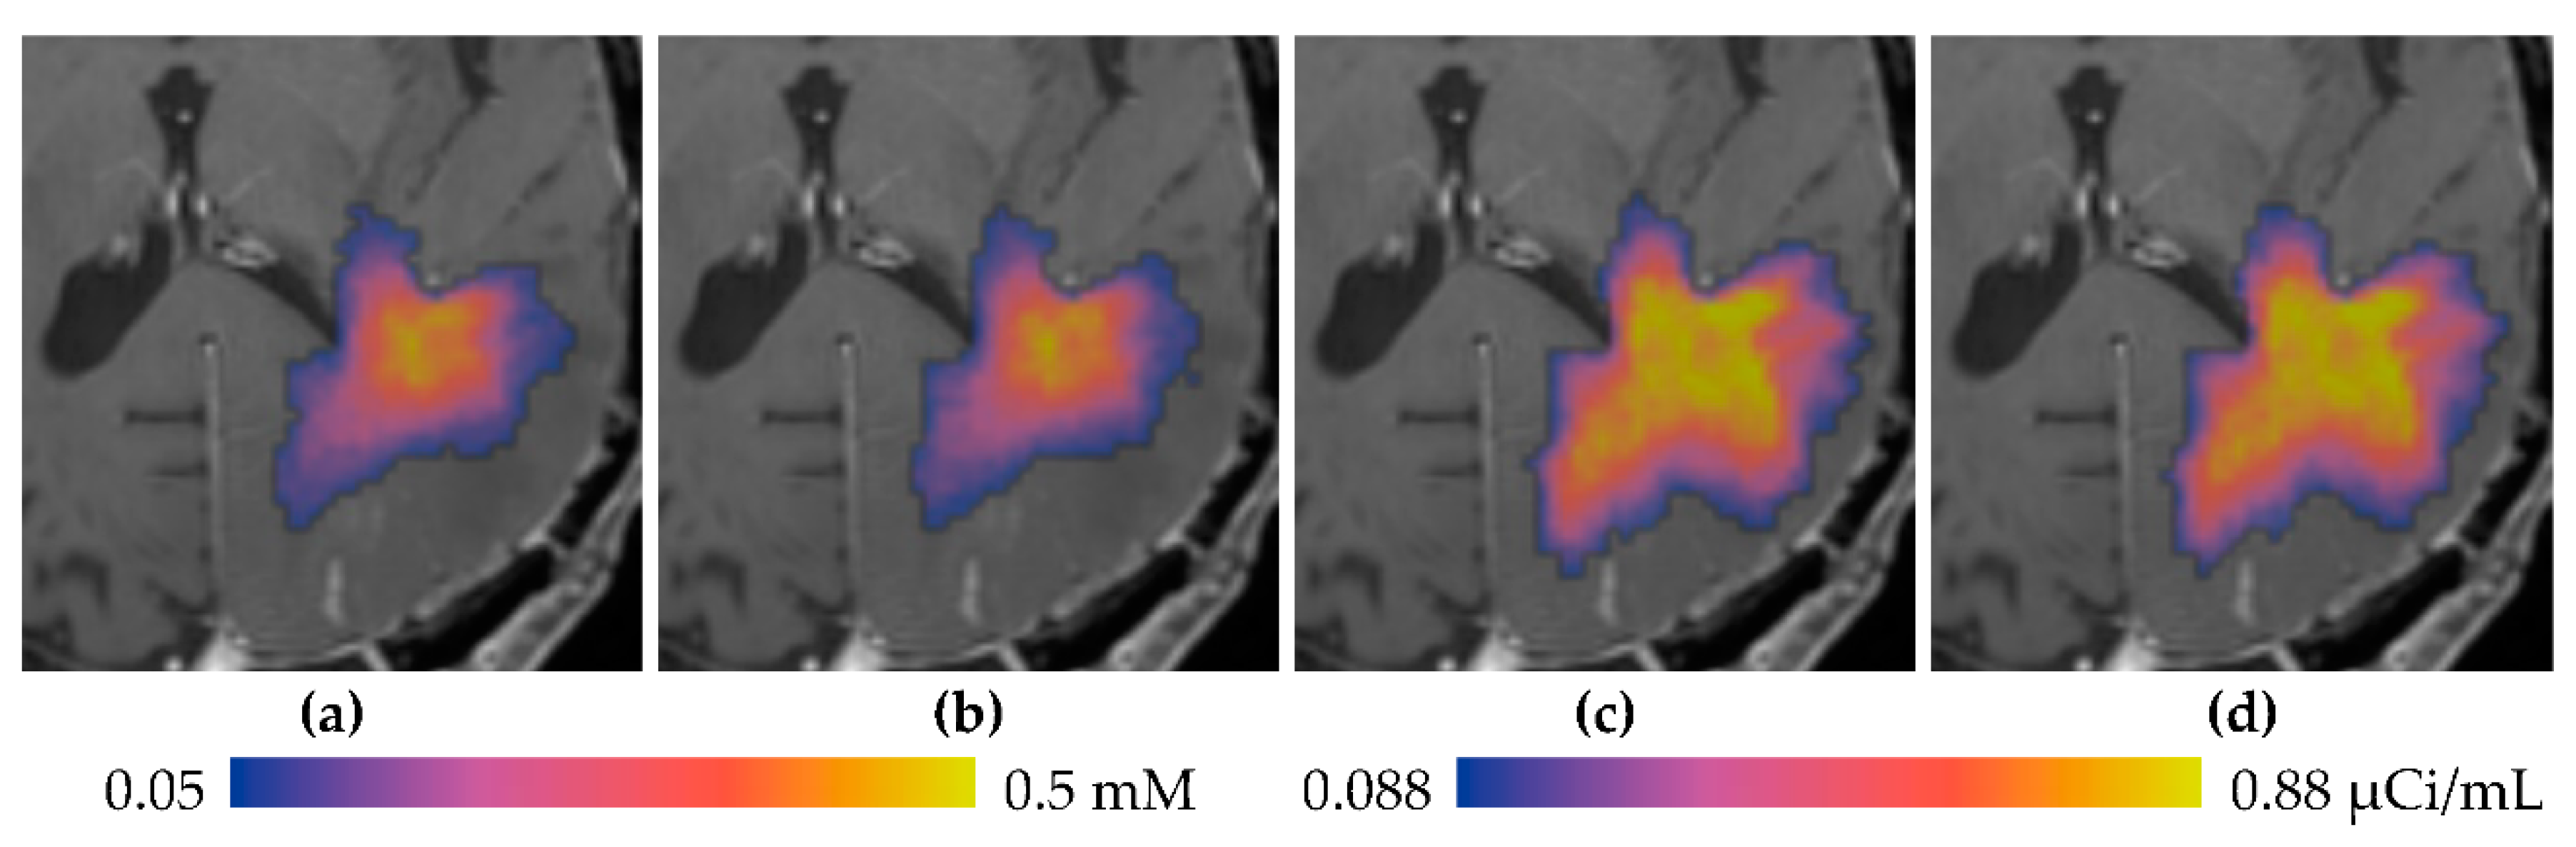

3.1. Descriptive Results

3.2. Statistics of Infusions and Simulations

3.2.1. Total Distribution Volume